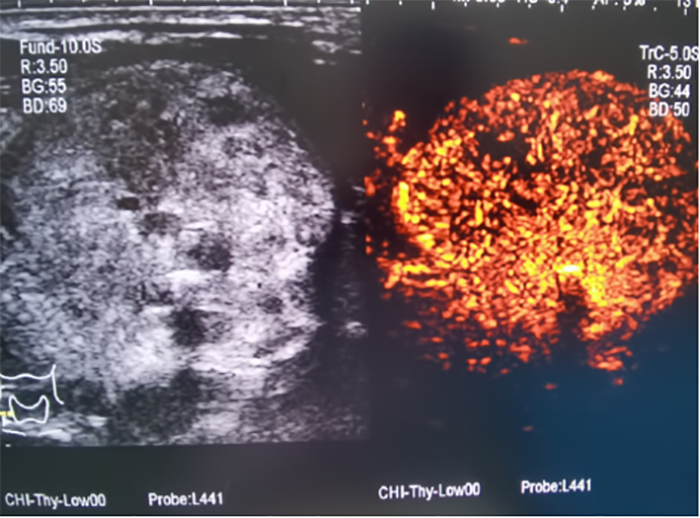

▲消融前,超声造影提示甲状腺结节内部血供丰富,活性大。